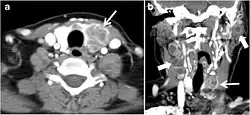

Fig. 4. A 45-year-old male patient presented with anterior mediastinal metastatic PTC lesions and occult primary on imaging. Histopathology examination of the resected thyroid gland revealed micro-foci of PTC; the largest, in the isthmus, measured 4 mm. a transverse greyscale ultrasound of the thyroid demonstrates homogeneous gland with normal echogenicity and size. No focal lesion or micro-calcifications. b Non-enhanced CT scan obtained as part of PET/CT examination shows a heterogeneous, large, relatively dense anterior mediastinal mass (white arrow) with peripheral calcification (arrowheads). Thyroid gland has normal CT appearance with no abnormal FDG uptake (not shown).[1]

Fig. 6. A 61-year-old female patient with locally aggressive PTC. an Enhanced axial CT scan of the neck demonstrates a heterogeneous infiltrative thyroid mass. This mass diffusely involves the entire gland and circumferentially encases the trachea with involvement of bilateral tracheoesophageal grooves (white arrows). b, c Additional axial cranial images show right cricoid cartilage destruction (black arrows in b), right thyroid cartilage destruction (black arrow in c), right vocal cord paralysis (white arrows in b), and bilateral cervical lymphadenopathy (arrowheads).[1]